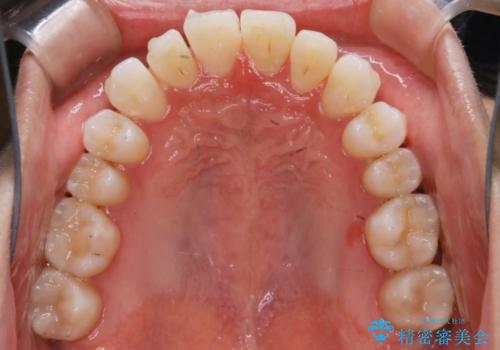

【非抜歯】八重歯を治す マウスピース矯正

- 前歯のガタつきの治療を主訴にご来院されました。

目立たない装置をとのご要望があったため、検査結果をふまえてインビザラインでの非抜歯矯正を行うこととなりました。

非抜歯での治療

抜歯をせずに歯のガタつきを治すためのスペースを作るために

①歯の遠心移動

②歯列弓の拡大

③IPR(歯を少し小さく削る)

この3つの方法を複合的に組み合わせて治療を行いました。

抜歯をせずとも笑った時の歯の見え方が劇的に変化していることが分かります。